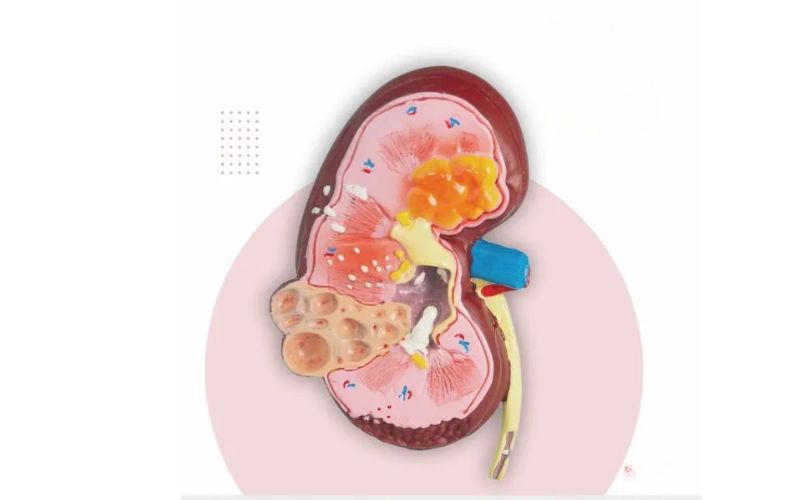

Kidney biopsy

A kidney biopsy is a diagnostic procedure where a small sample of kidney tissue is extracted to examine under a microscope. It helps determine the cause, ,